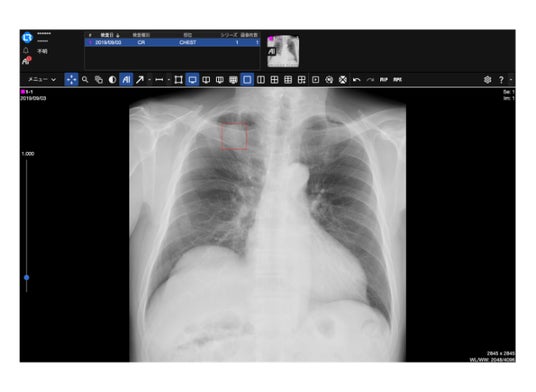

※ 製品表示例:「AI」ボタンをおすとEIRL解析結果が表示されます。